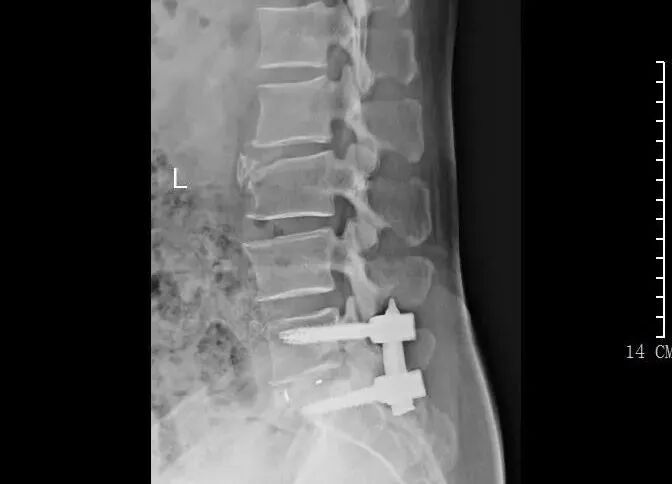

3月前,患者再次出現(xiàn)腰腿痛疼痛癥狀,夜不能寐,嚴重影響生活?;颊邚?fù)查了腰椎磁共振,結(jié)果提示:腰5/骶1椎間盤突出復(fù)發(fā),明顯壓迫神經(jīng)。經(jīng)過口服消炎止痛藥、理療等保守治療,患者腰腿痛無明顯改善,于是再次入住惠州三院脊柱外科,被診斷為復(fù)發(fā)性腰椎間盤突出癥。

核磁共振檢查影像

術(shù)后內(nèi)固定情況